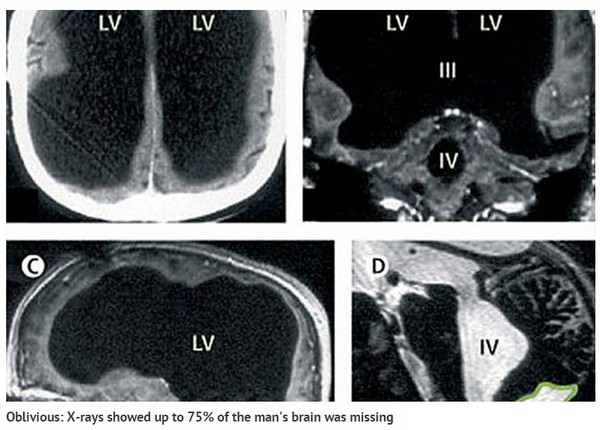

法男大脑缩小了约50~75%的面积。

法国一名44岁男子因脚痛就医,没想到医生在检查时,意外发现他